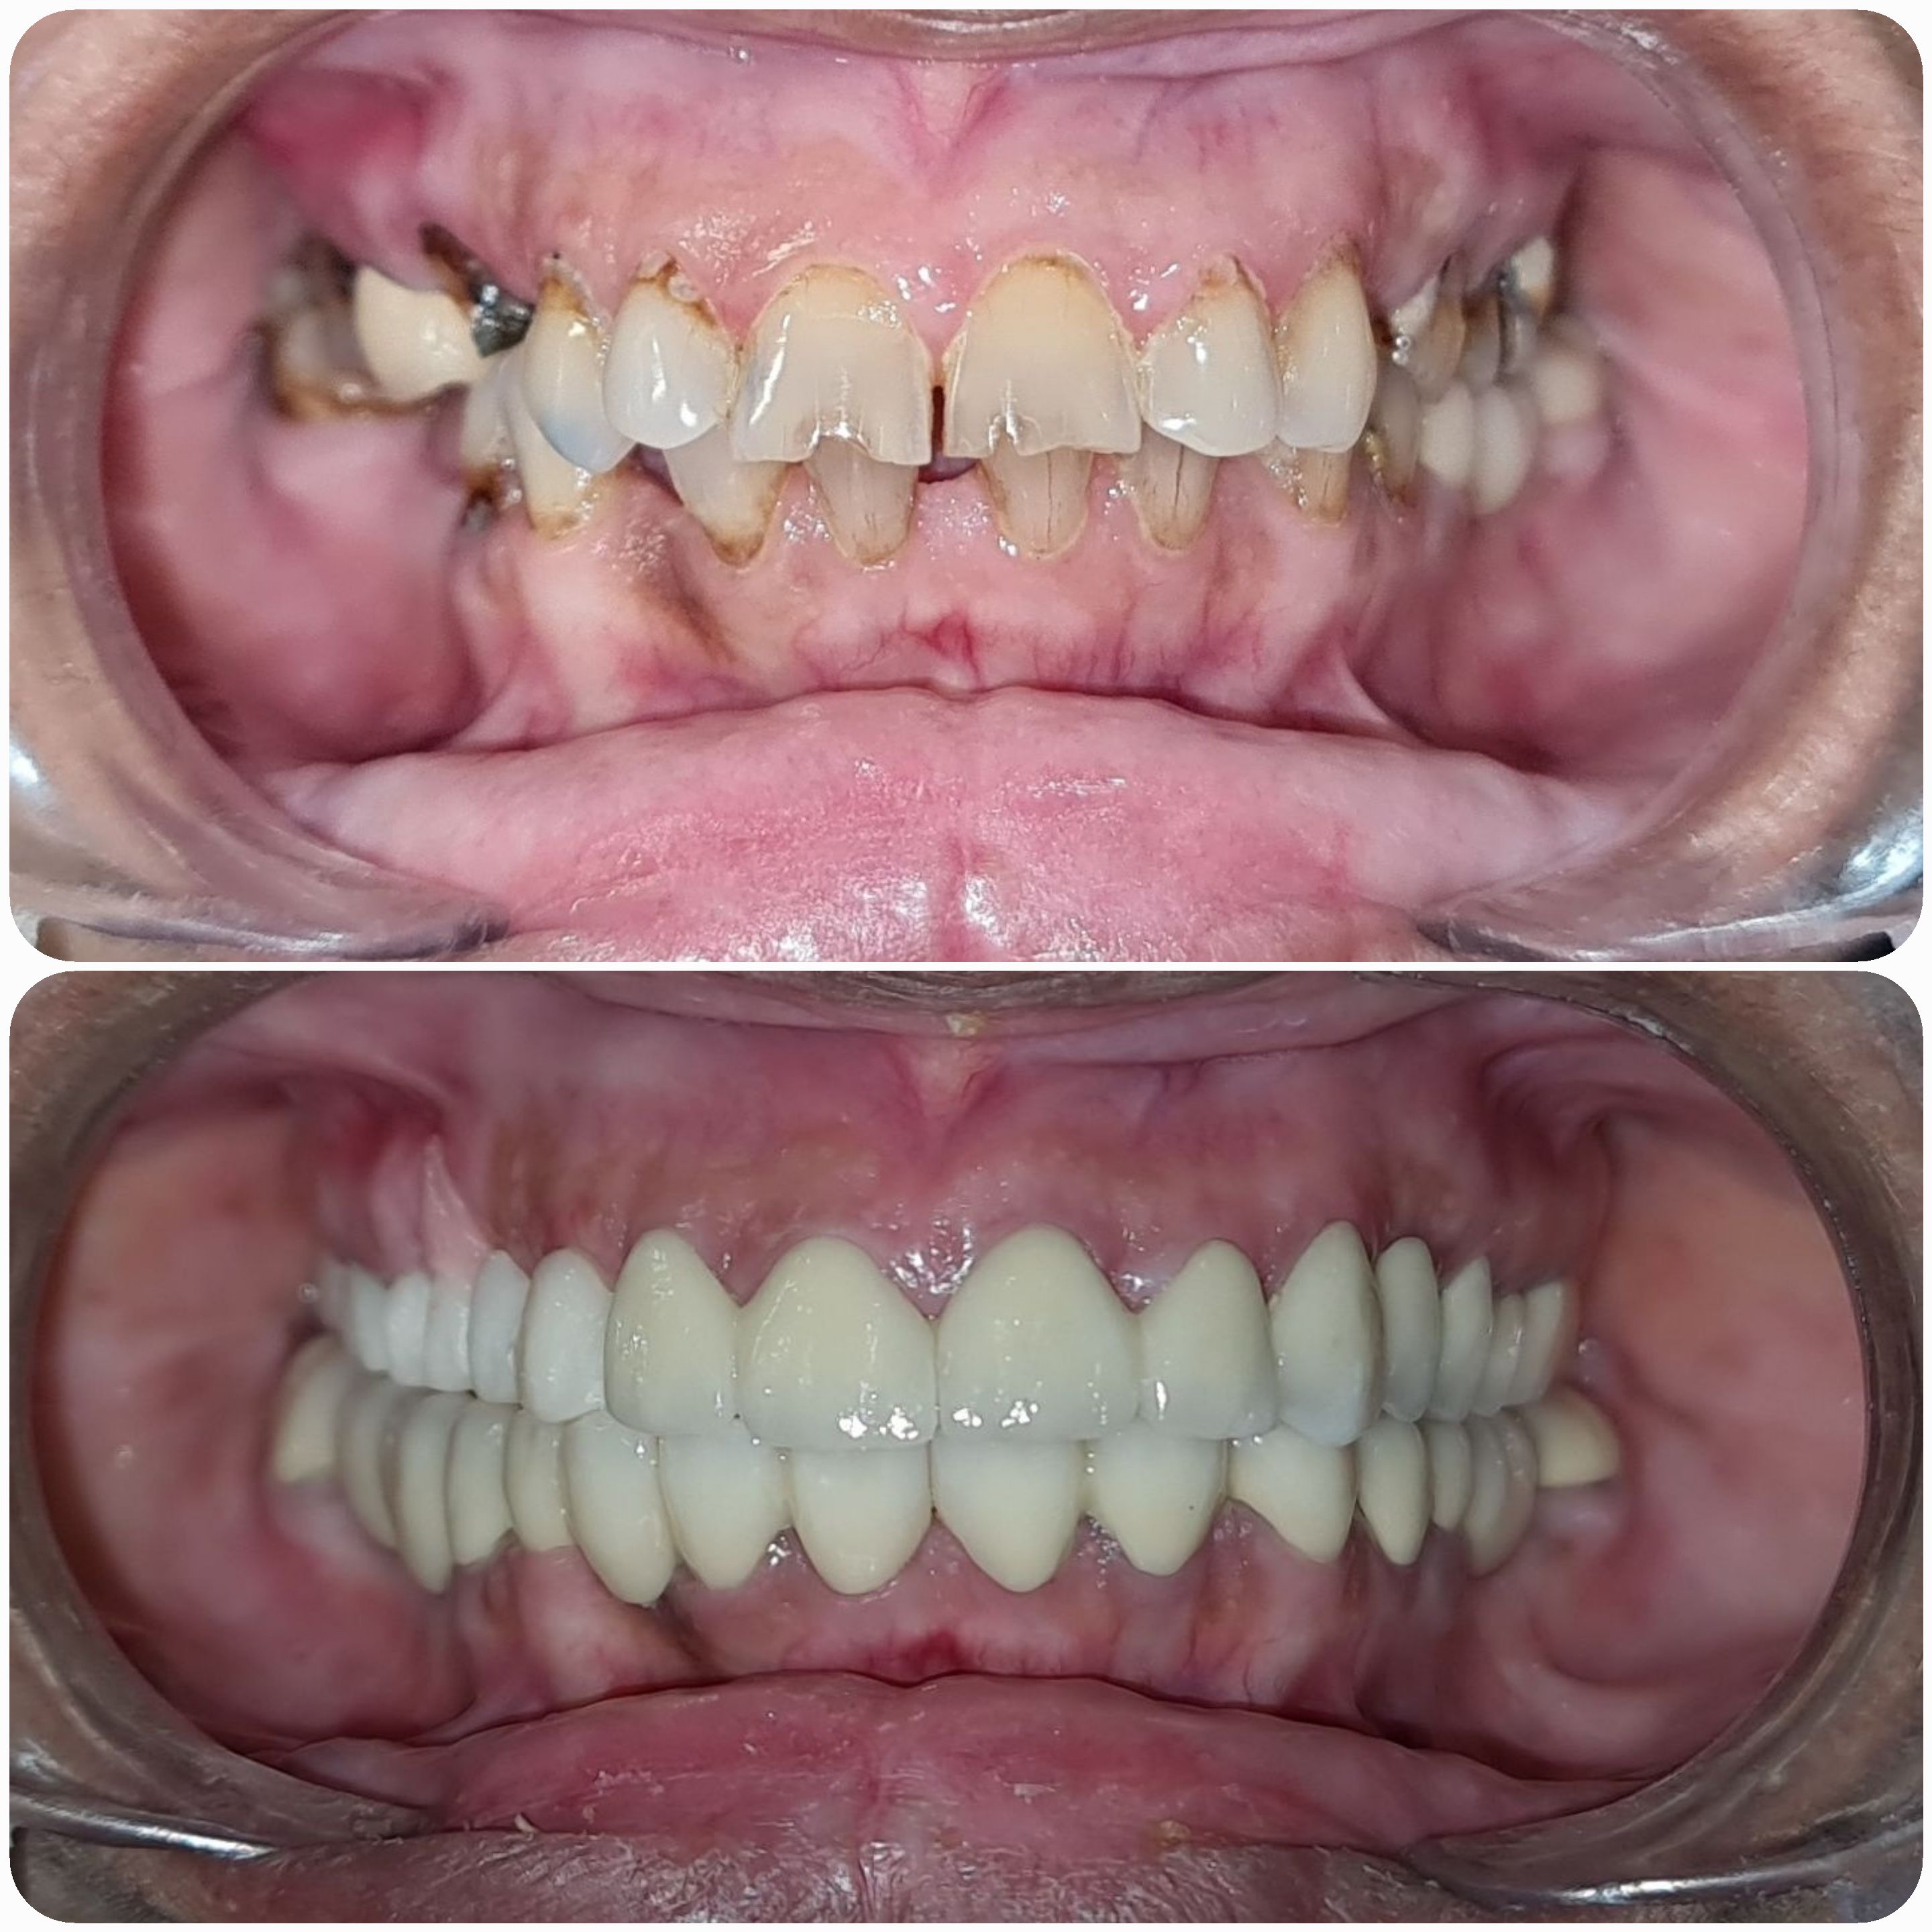

Cases